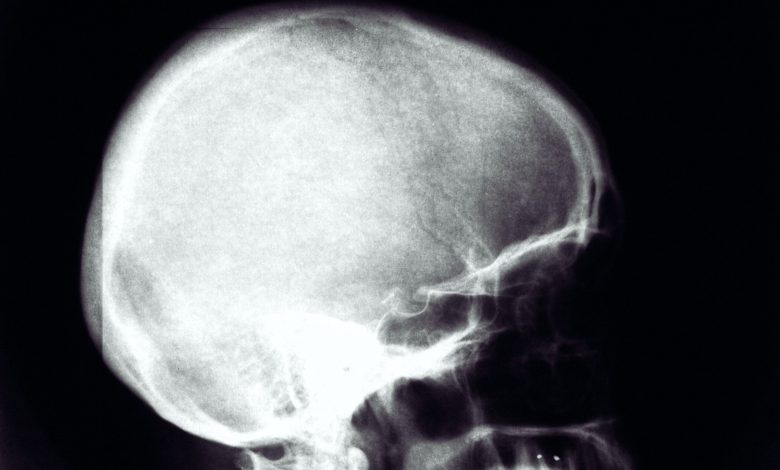

Um dos resultados potencialmente fatais do traumatismo craniano é o chamado hematoma subdural agudo – um sangramento que ocorre entre o cérebro e o crânio e pode levar ao acúmulo de pressão. Tais hemorragias requerem cirurgia para estancar o sangramento, remova o coágulo de sangue e alivie a pressão.

Atualmente, existem duas abordagens para essa cirurgia. Uma abordagem é a craniectomia descompressiva, que envolve deixar uma seção do crânio para fora – que pode ter até 13 cm de comprimento – para proteger o paciente do inchaço cerebral, frequentemente observado nesse tipo de hemorragia. O crânio perdido normalmente precisará ser reconstruído e, em alguns centros de tratamento, o próprio osso do paciente será substituído vários meses após a cirurgia, enquanto em outros centros uma placa manufaturada é usada.

A segunda abordagem é uma craniotomia, em que a seção do crânio é substituída após a hemorragia ter sido estancada e o coágulo sanguíneo removido. Essa abordagem evitará a necessidade de uma reconstrução do crânio mais adiante.